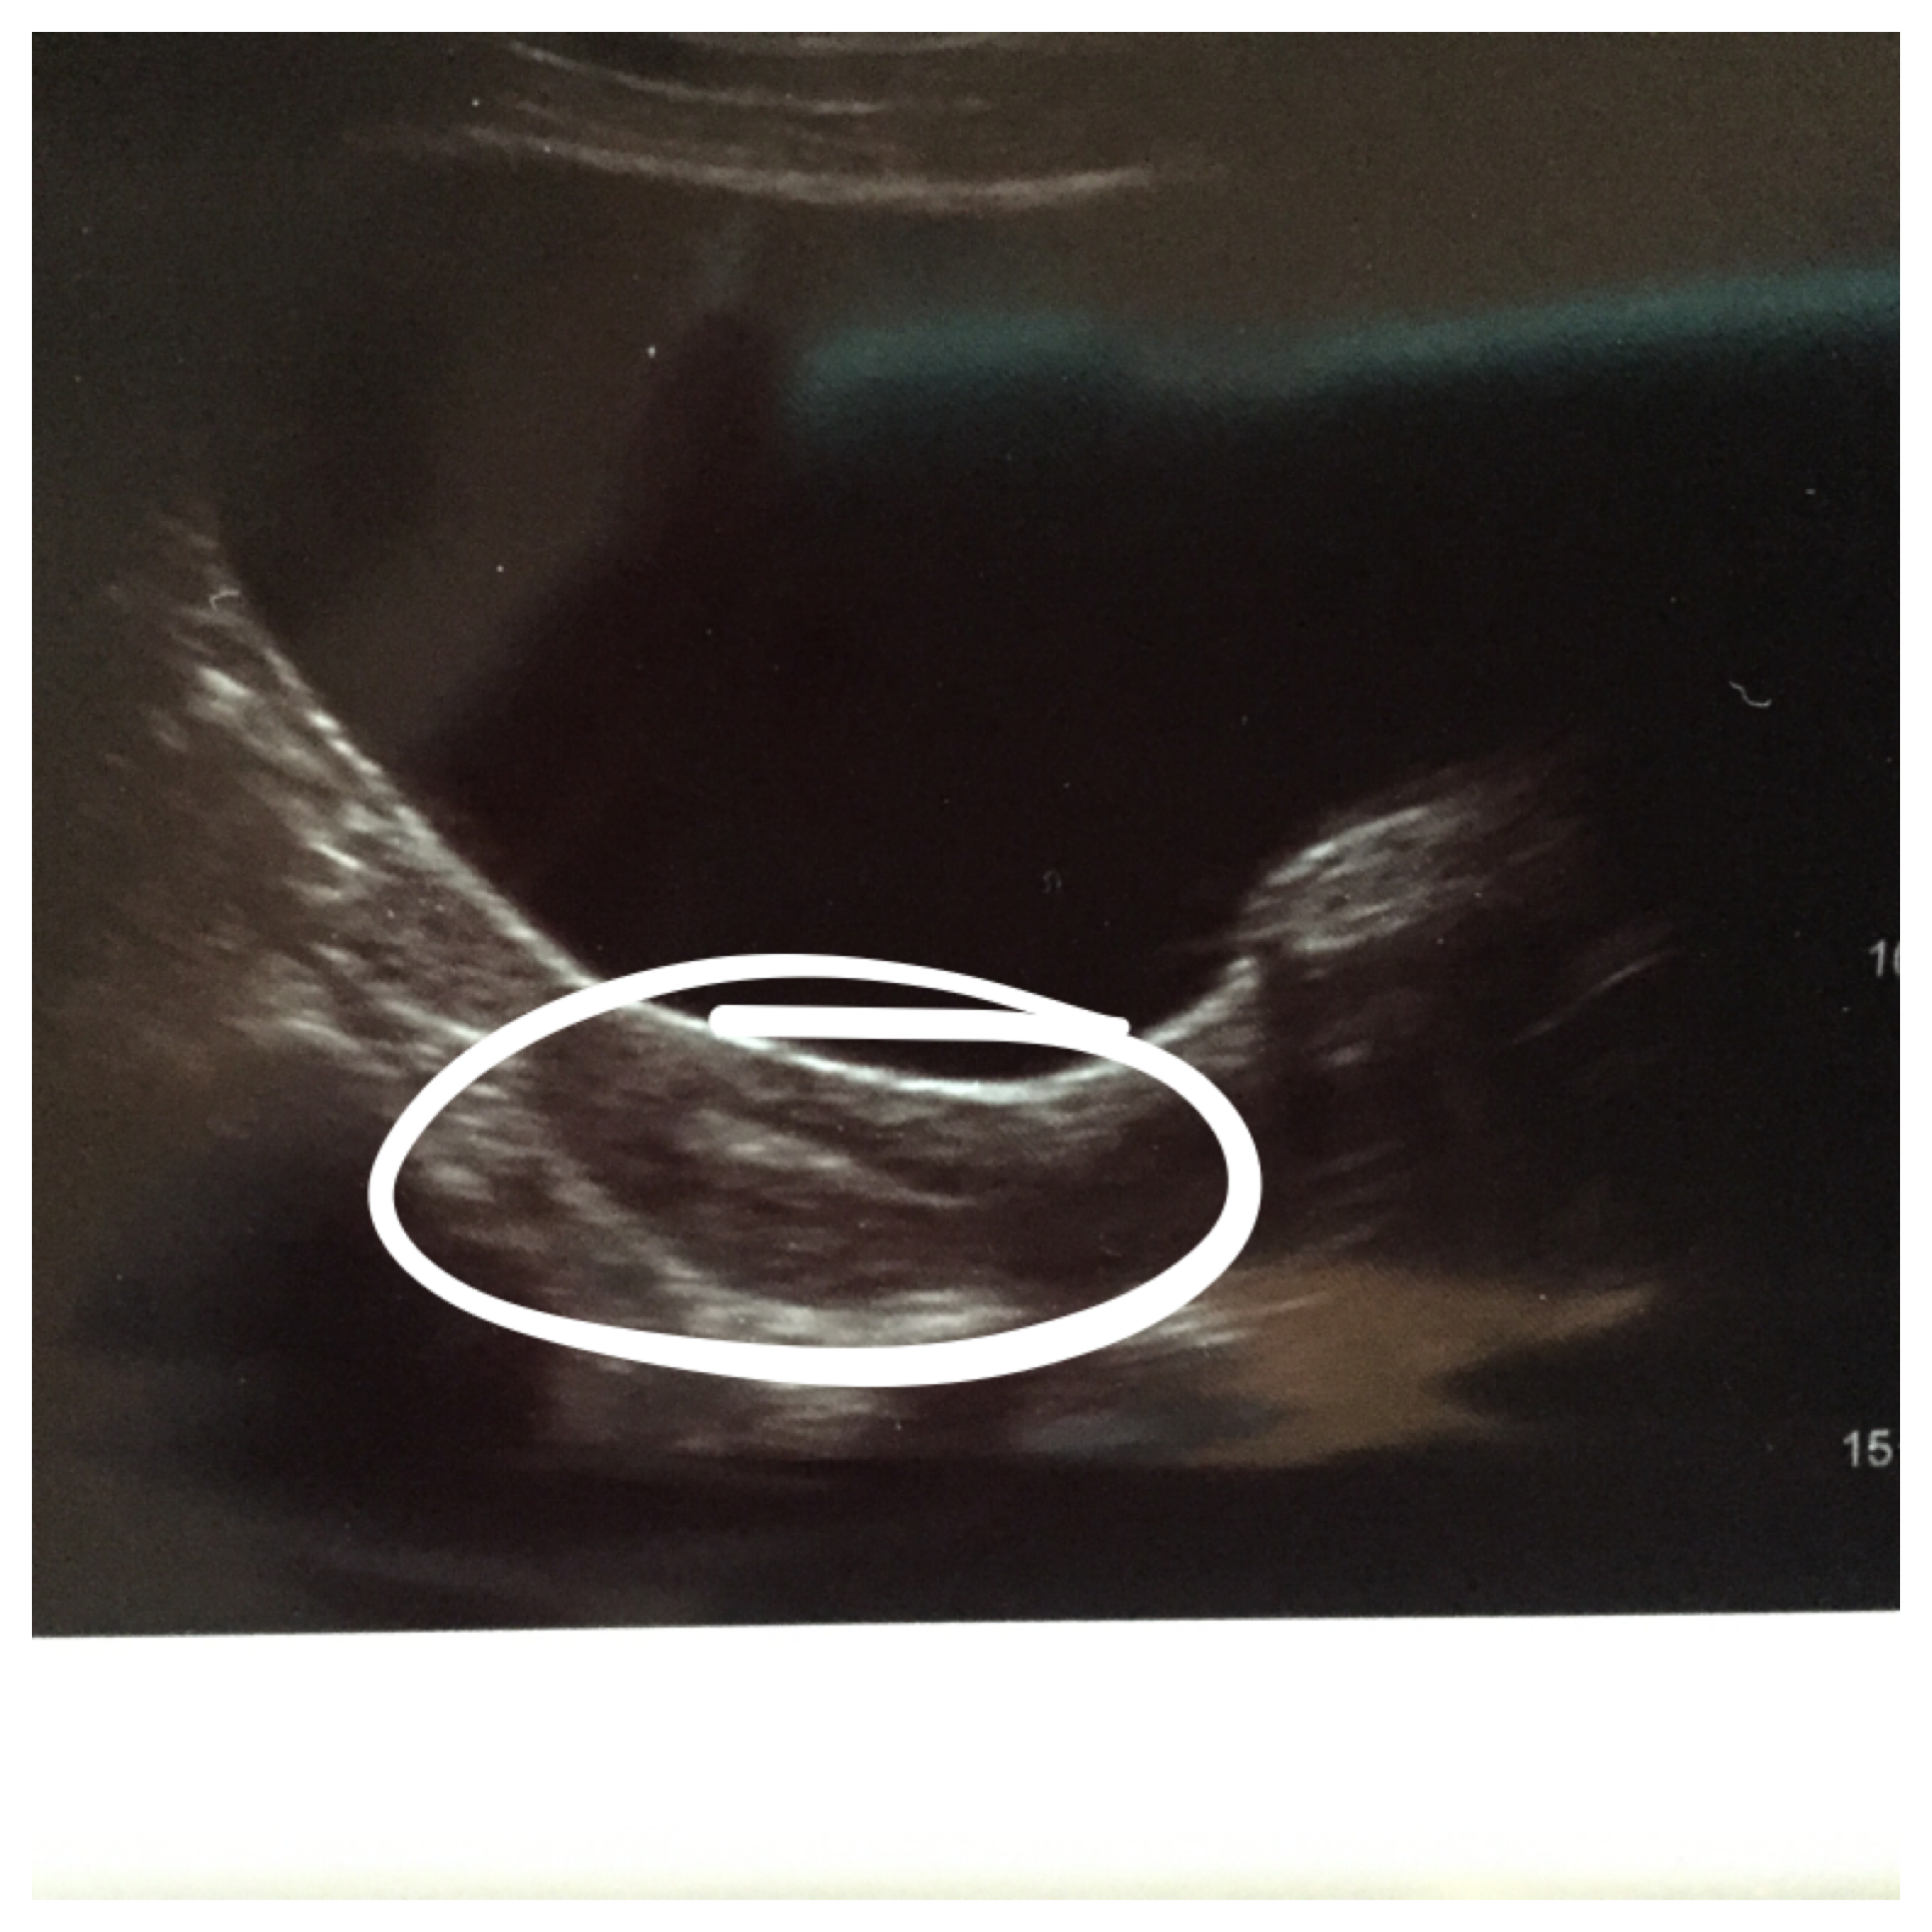

And here they go:

You can see two little white dots – that’s the air pockets pushing the embies into their new home! All around it is my lining where they’ll implant in the next 24-36 hours! I hope they find a ‘Home Sweet Home’ sign soon!!